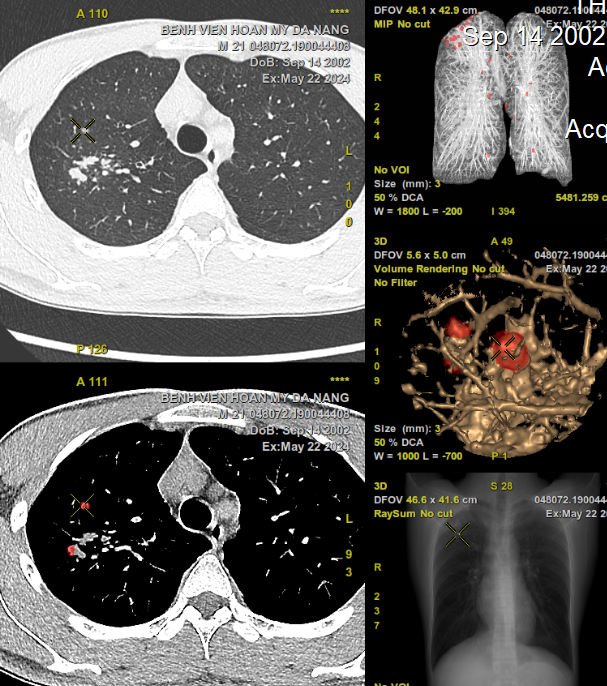

Hình ảnh CT 256 lát cắt phổi hiện đại có ứng dụng trí tuệ nhân tạo (AI) giúp phát hiện gần như tất cả các tổn thương dù có kích thước nhỏ

Bệnh viện Hoàn Mỹ Đà Nẵng vừa trang bi hệ thống chụp CT 256 lát cắt hai mức năng lượng ứng dụng trí tuệ nhân tạo (AI) có khả năng phát hiện các nốt phổi nhỏ kích thước cỡ 2 mm. Kết quả được lọc và đọc tự động, bác sĩ sẽ dễ dàng sàng lọc những tổn thương nghi ngờ. Làm gia tăng tính chính xác, hạn chế bỏ sót tổn thương, tiết kiệm thời gian và nâng cao hiệu quả điều trị kịp thời cho người bệnh. Nhờ khả năng chẩn đoán sớm mà các bác sĩ có chiến lược điều trị phù hợp hoặc phẫu thuật cắt bỏ các khối u ác tính khi còn nhỏ, giúp nâng cao cơ hội sống cho người bệnh.